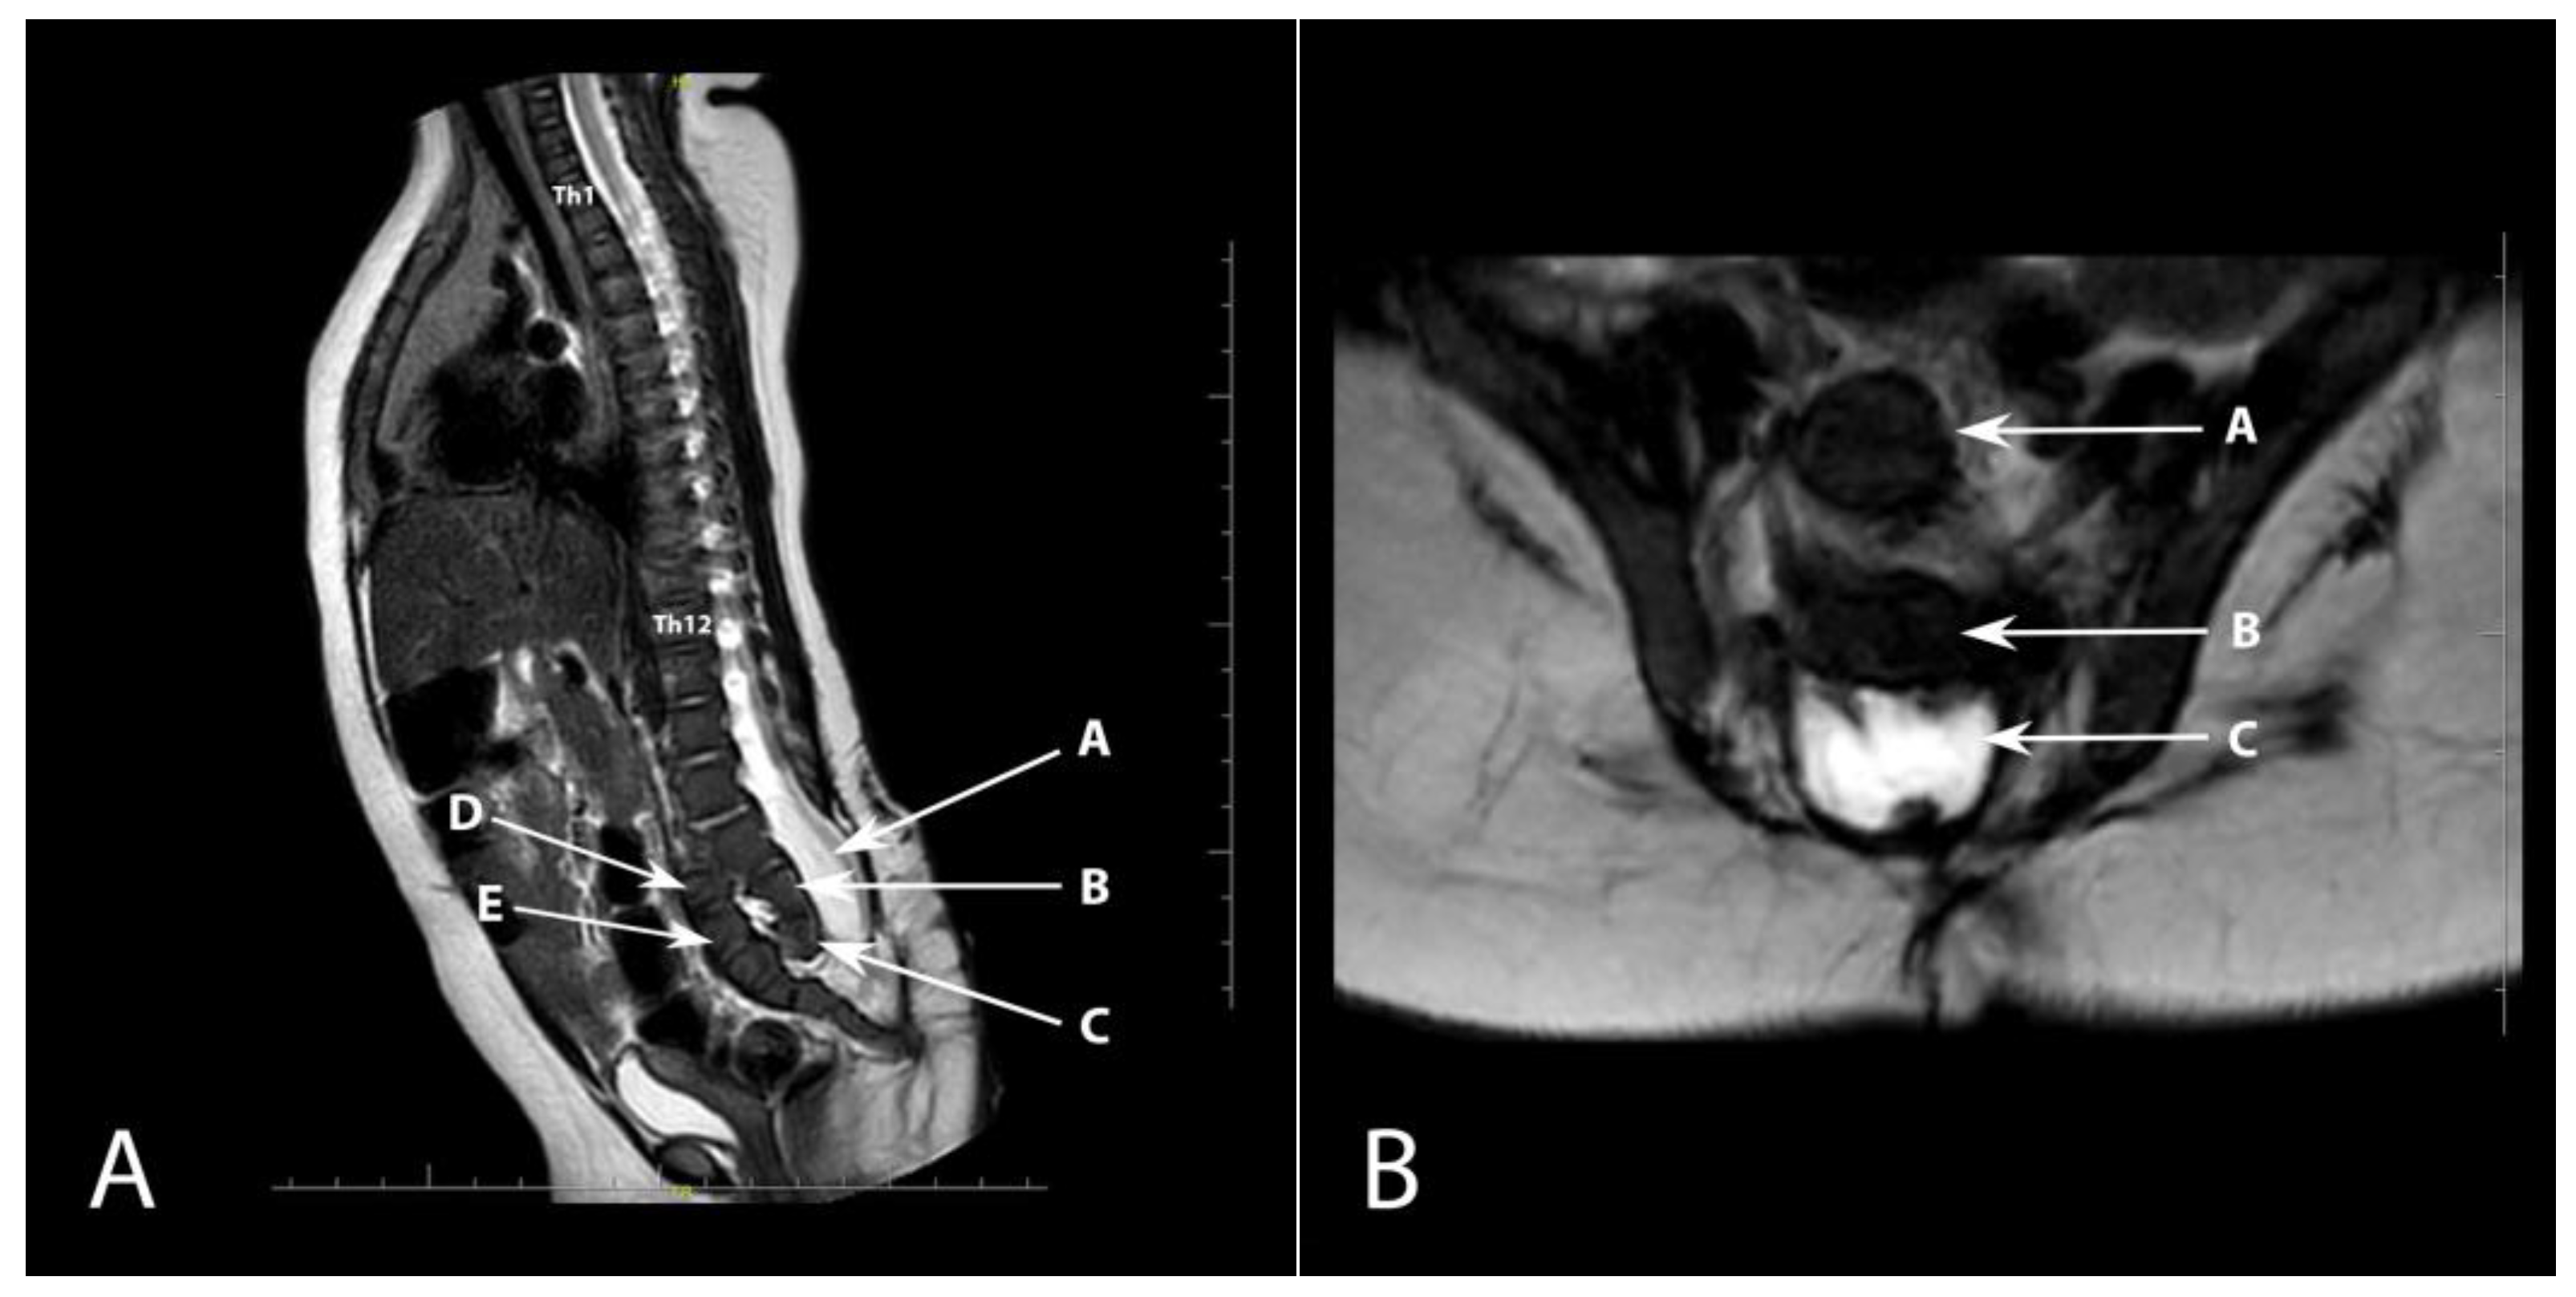

Congenital Anterior Dislocation of the Sacrococcygeal Bone in a Newborn

Fabijan, A.; Polis, B.; Zakrzewski, K.; Zawadzka-Fabijan, A.; Korabiewska-Pluta, S.; Nowosławska, E. Congenital Anterior Dislocation of the Sacrococcygeal Bone in a Newborn. Diagnostics 2023, 13, 2108. https://doi.org/10.3390/diagnostics13122108